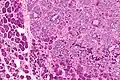

This tumour is characterised by biphasic tubular structures composed of inner ductal and outer clear myoepithelial cells.

The histologic differential diagnosis includes adenoid cystic carcinoma and pleomorphic adenoma.

High mag.